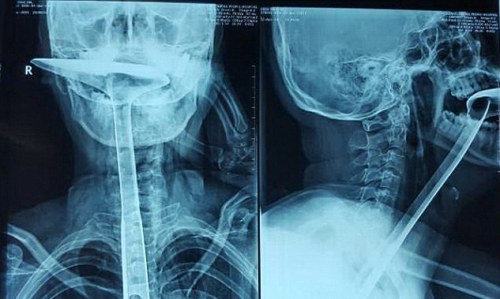

Hình ảnh X-quang cho thấy bàn xẻng dài trong thực quản bệnh nhân. Ảnh: Imaginechina/Rex Shutterstock. |

Phải trải qua hai ca phẫu thuật các bác sĩ mới lấy chiếc xẻng nấu ăn ra khỏi cổ họng thành công nhưng họ buộc phải cắt đi đoạn thực quản dài 20 cm đã bị tổn thương không thể phục hồi. Bệnh nhân tạm thời qua cơn nguy kịch nhưng thực quản bị tổn thương nặng.

Đầu tiên, cô thử với các ngón tay, sau đó là 3 chiếc đũa, cả ba đều bị gãy. Guan quyết định dùng vật lớn hơn và cho xẻng nấu ăn bằng bạc dài tới 30 cm vào miệng, rồi chọc dần xuống cổ họng.